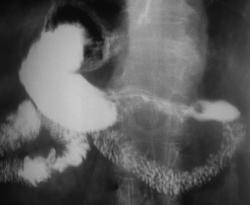

На иллюстрациях 3, 4, 5, 6 (с компрессией «мягким» дистинктером» четко дифференцируется неровность малой кривизны на измененном участке, нишеподобное «депо контрастного вещества» на рельефе. Фиксируется некоторая ригидность желудочной стенки на измененном участке.